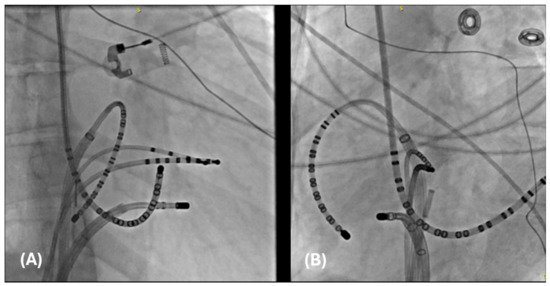

4.2.1. Cases

4.2.2. Case 1

4.2.3. Case 2